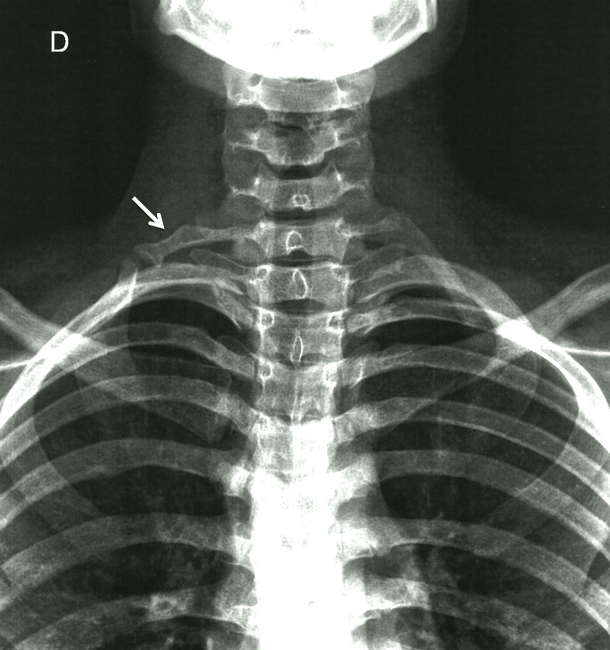

The hyperabduction maneuver (Wright test) showed no change in the radial pulse. The Adson test was also negative. Light percussion of the cubital nerve in the wrist caused a tingling sensation, which is a positive Hoffman sign. The cervical spine X-ray showed bilateral cervical ribs, more evident on the right side (Figure 1).

Figure 1. Anteroposterior X-ray film of the cervical spine showing bilateral cervical ribs more evident on the right side (arrow).